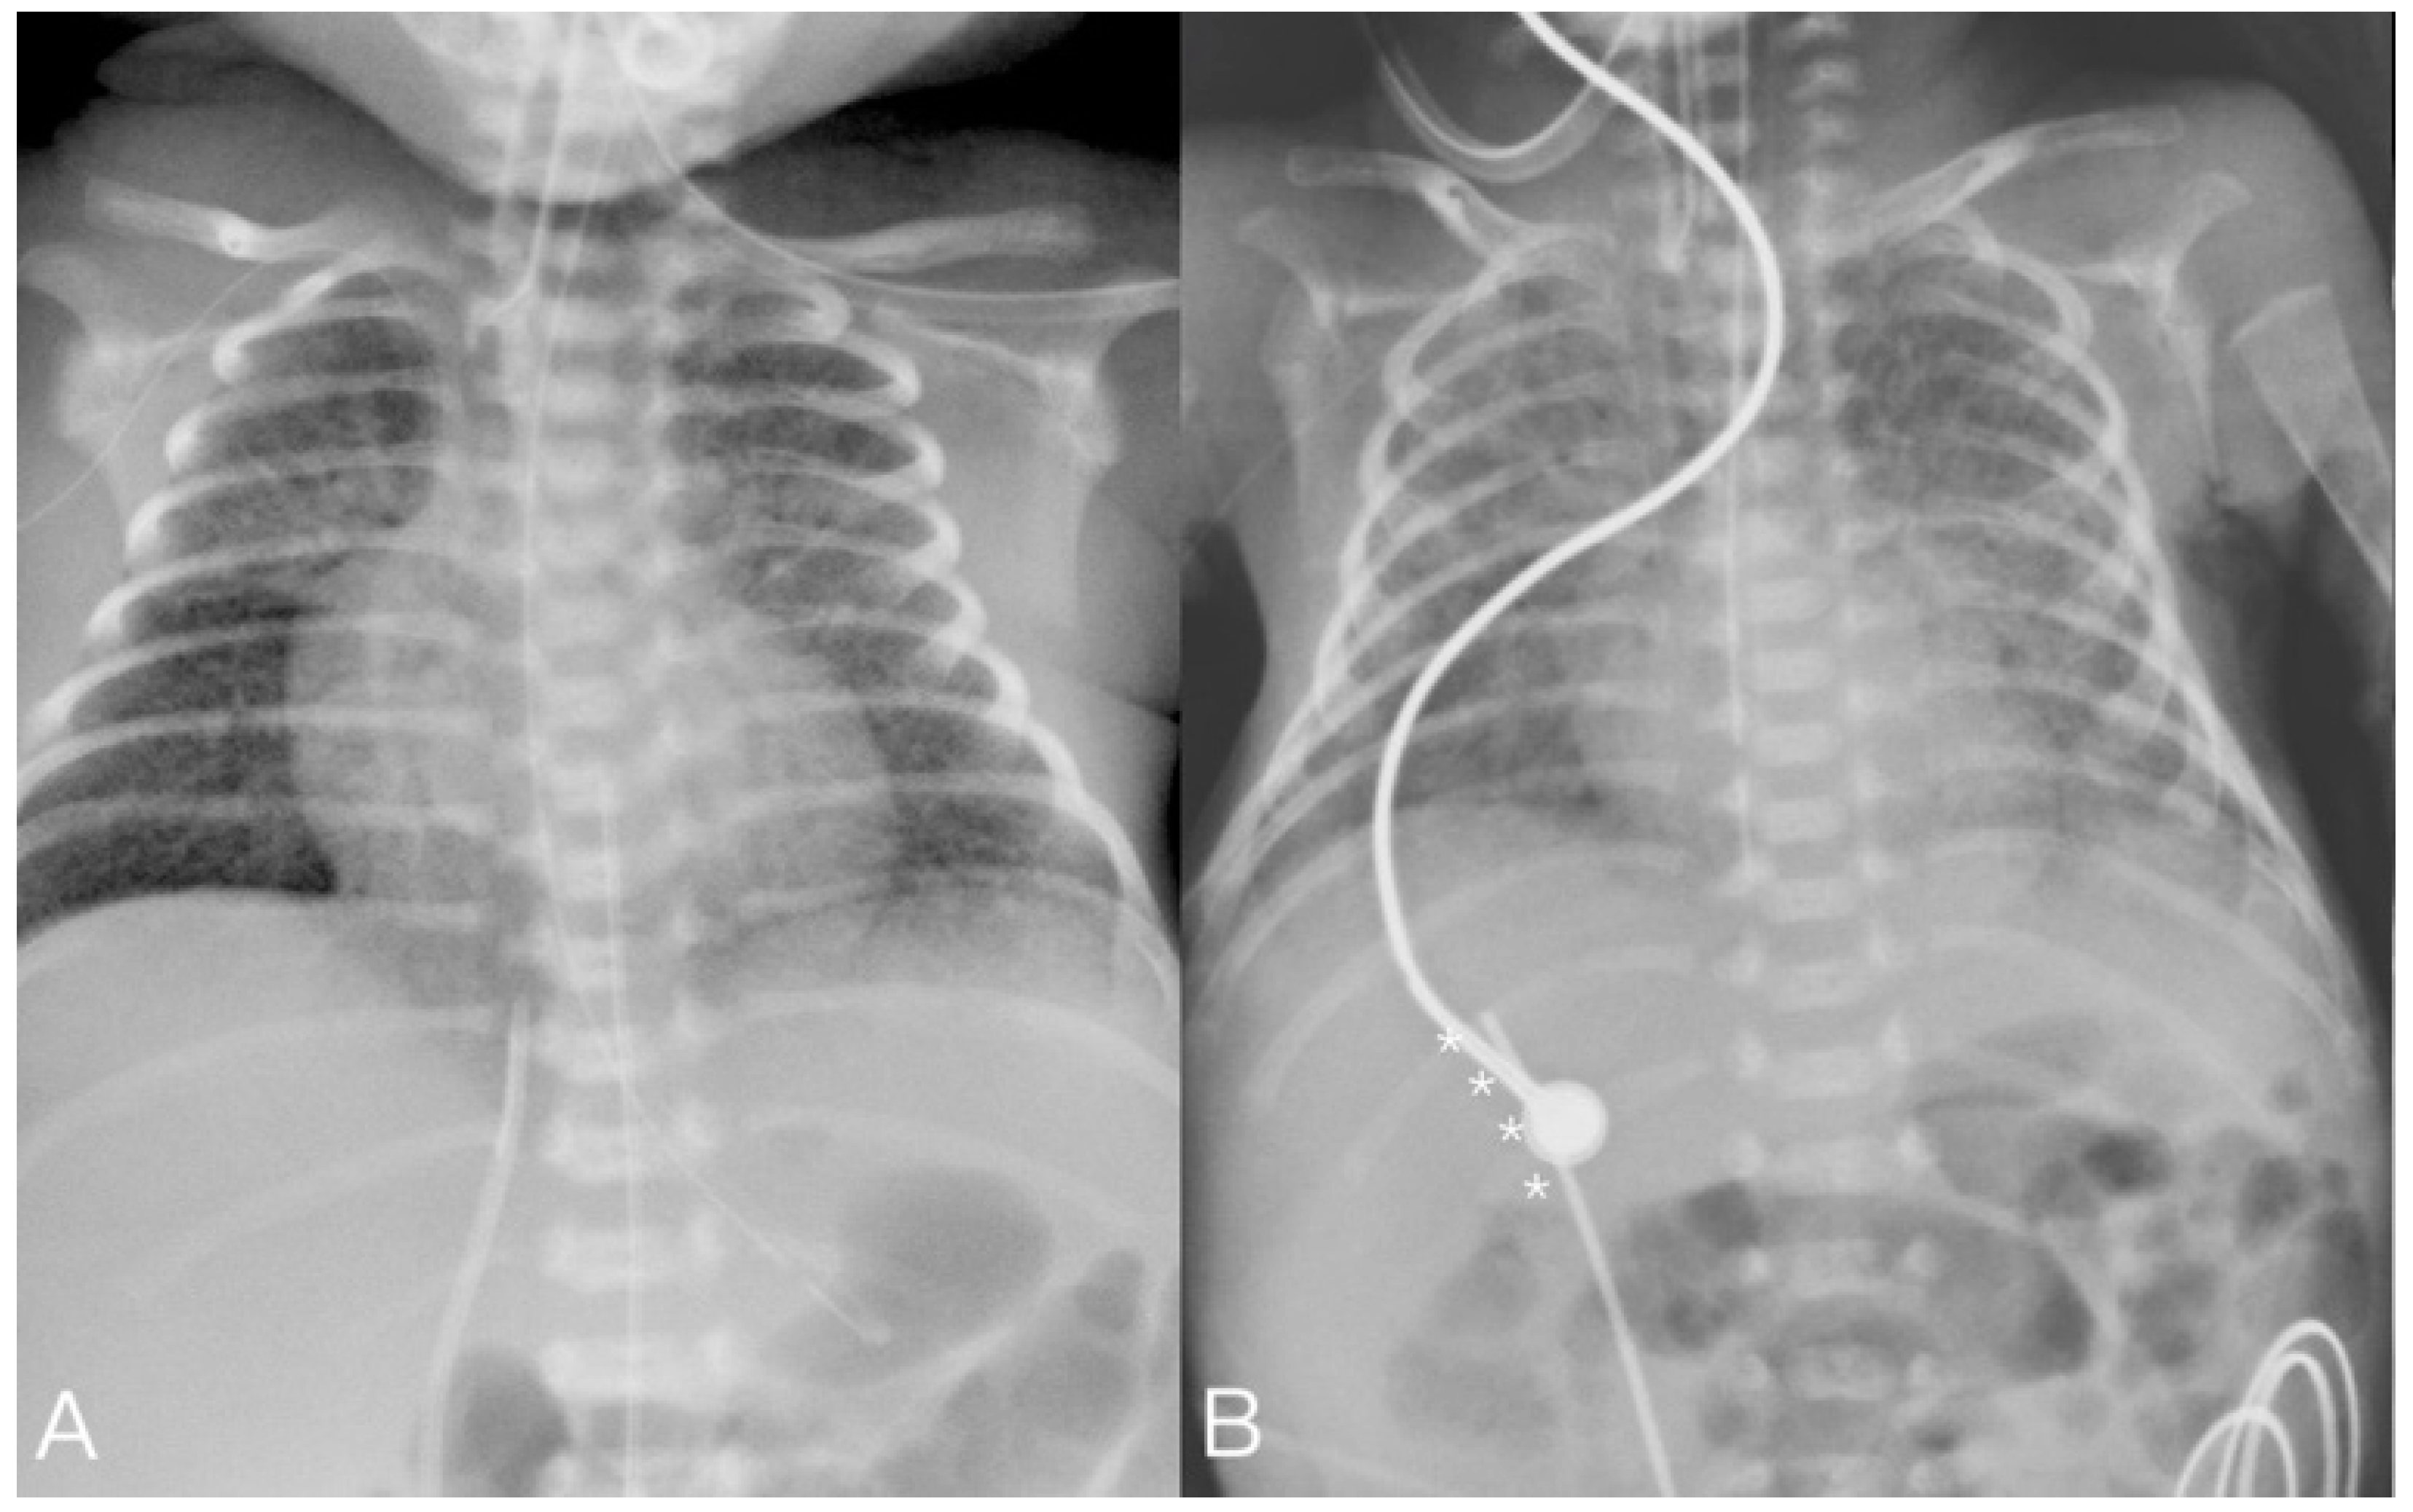

| 4 * | 32 + 6 | 2360 | M | 9 | 2356 | PDA/renal hypoplasia | 4/11 |

| 4 | 4 | PDA occluder | 4 | Success | ADOIIAS 5-4 | 19 m 54 s | 57 | Intraabdominal hemorrhage | Expired due to CVVH complication |

| 5 | CVVH | 11 | Success | ||||||